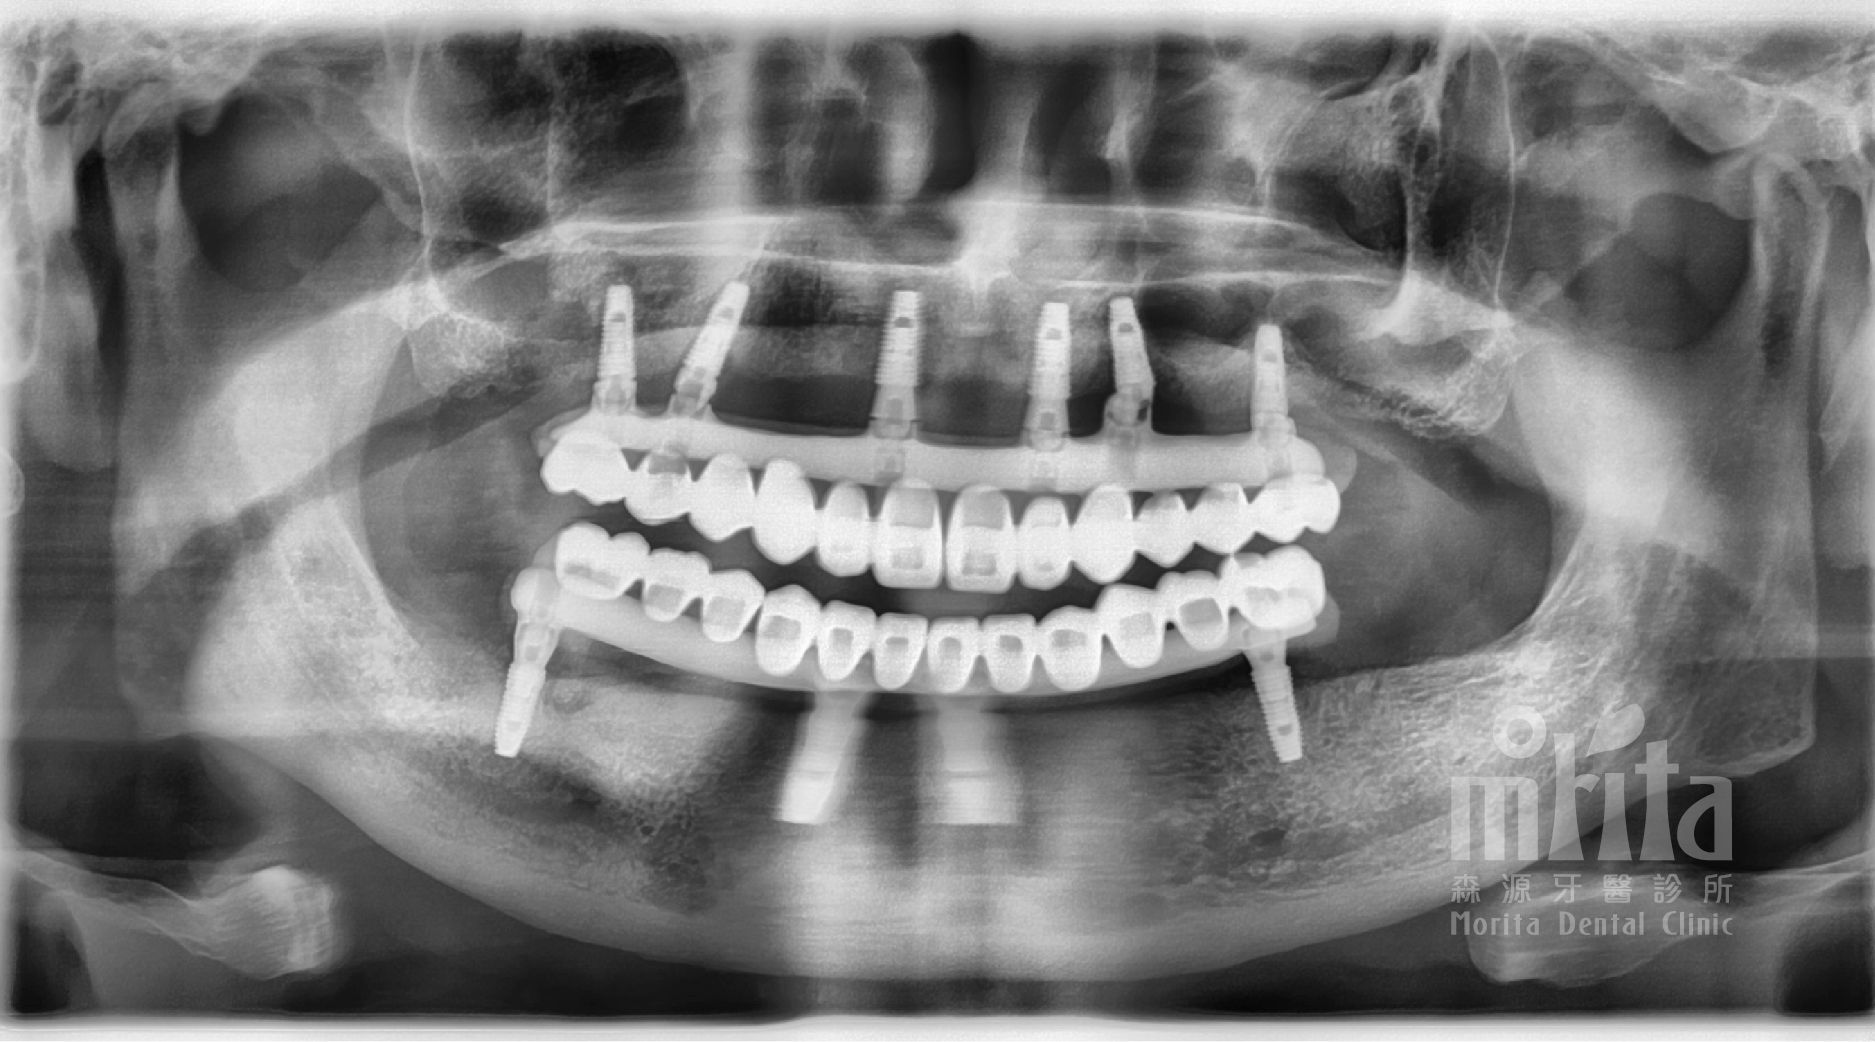

正式假牙完成,賴伯伯再次重拾自信的笑容,吃得開心,自然生活也跟著快樂起來。